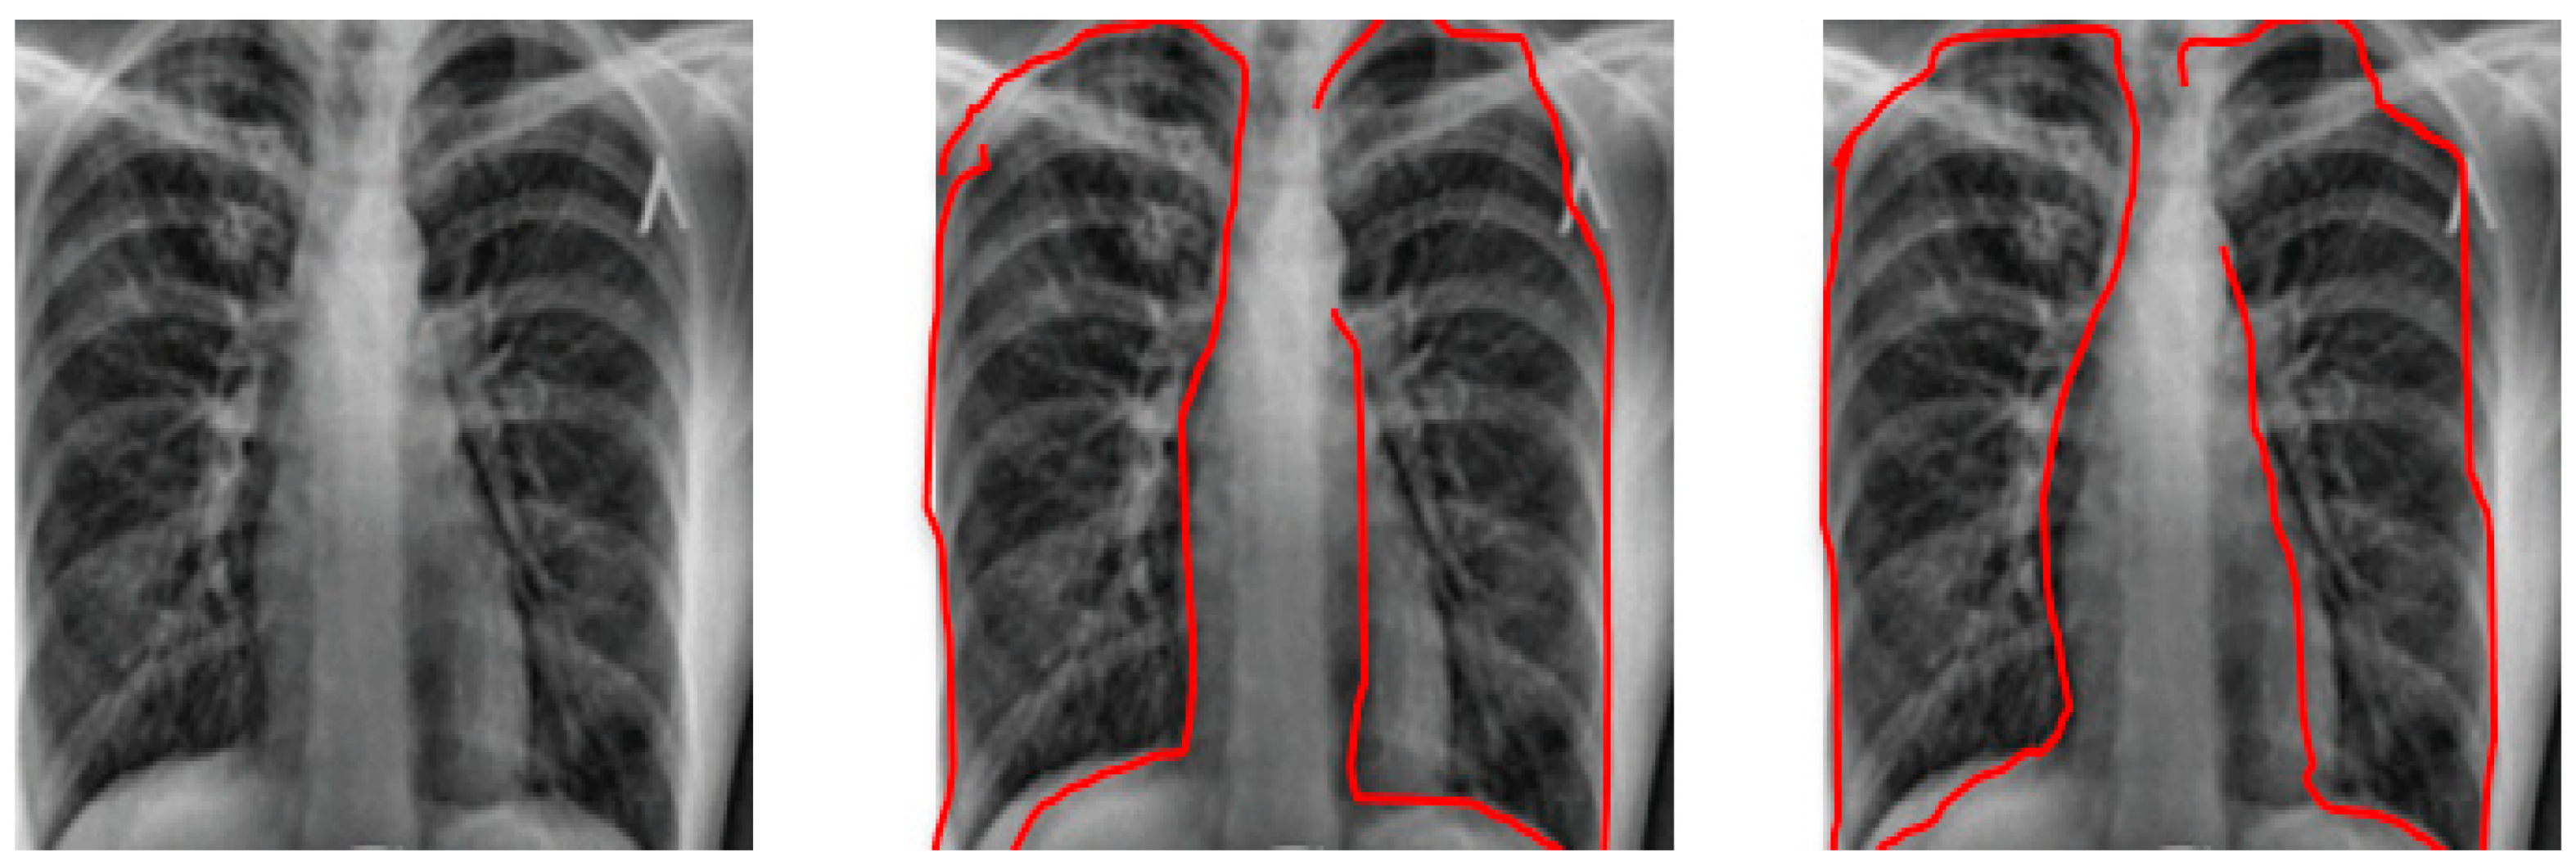

Both BoxENet and the improved BoxENet CNNs were trained and tested on the testing subset for the X-rays segmentation process. The highest accurate parameters for X-ray segmentation are depicted in Table 7. In Figure 5, testing X-rays radiography and associated ground truth are displayed. Segmented pulmonary radiography was produced by both BoxENet CNNs for the Kaggle database. It is depicted that the improved BoxENet outperformed the original BoxENet in the segmentation process of the pulmonary areas from the X-ray radiography.

Figure 5. X-ray radiography, with segmented Pulmonary original BoxENet and Segmented Pulmonary Improved BoxENet.